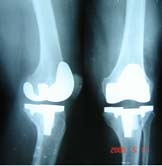

(二)X线检查

关节周围软组织肿胀影,骨质疏松,以后关节间隙变窄,骨盾破坏,反应发现有质增生。晚期关节呈纤维性或骨性融合,死骨形成,关节脱位或间脱位。X线检查时,在早期由于关节液增加而关节囊肿胀,间隙增宽,骨端逐渐有脱钙现象。如关节面软骨有破坏,则关节间隙变窄。有时可讲发骨骺滑脱或病理性脱位。较晚期,关节面下骨质呈反应性增生,骨质硬化,密度增加。最后关节软骨完全溶解,关节间隙消失,呈骨性或纤维性强直,或饼发病理性脱位。其X线表现为:

1. 早期关节内有化脓性炎症时,关节周围软组织常有充血及水肿,表现为软组织厚于健侧,层次不清。关节囊因关节内积液而膨胀,脂肪层被推移呈弧形。偶尔可见关节间隙轻微增宽,应与健侧对照,才不会漏诊。 医学百科网 | YxBaike.Com

2.关节间隙狭窄化脓性细菌进入关节后首先引起的滑膜炎。渗出液内含有大量中性白细胞。白细胞死亡后所释放出的大量溶蛋白酶、很快地溶解关节软骨。根据关节软骨被破坏的程度,常于发病后短期内出现关节间隙狭窄,甚至完全消失。

3.关节面改变关节软骨被破坏后,即可进一步破坏软骨下骨质。最早出现在关节面的相互接触部分,即负重部分。表现为关节面模糊和不规则。继而形成较大的破坏区,形成死骨。由于机体的修复作用,破坏区周围因骨质增生而密度增大,关节边缘有唇样骨质增生。当骨小梁贯穿关节间隙以联接两侧骨关节面时称之骨性强直。

4.关节软骨及骨质破坏严重时可引起脱位或半脱位一般青少年和成人,常因关节软骨破坏形成骨性强宜,而儿童多发生骨端的破坏,吸收,引起病理性脱位。

6. X线摄片早期关节间隙变宽,较晚期间隙变窄,晚期关节破坏,关节间隙消失等表现,早期应与对侧。关节对比。 医学百科网 | YxBaike.Com